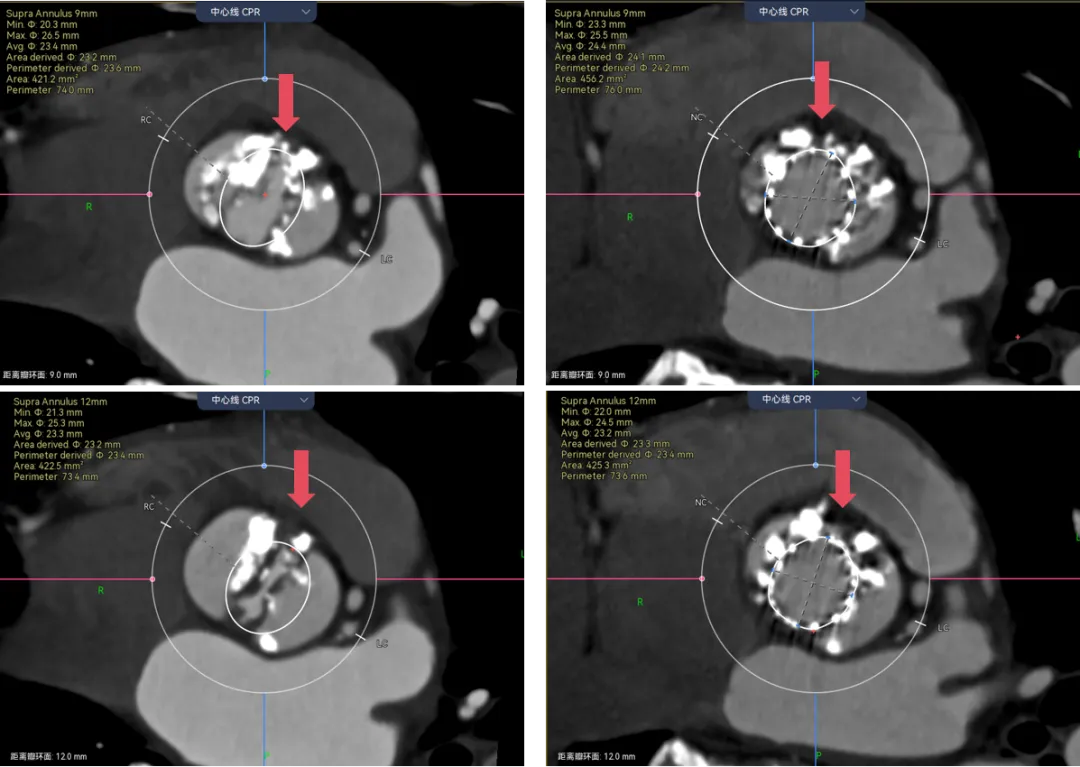

遇见这种三叶瓣,边缘都有很重钙化的你会怎么画呢?瓣叶能推开么?要不要把边缘占满?这里考验的就是对钙化程度的综合理解了。刚刚也说了,瓣叶中间的钙化一般是可以推动的,除非连上了基底部有一大块的。而边缘的钙化,瓣膜往往没法占满。这就是钙化导致的瓣周漏的原因。

让我们来看看术前和术后预测的对比,预留的交界区域完全正确,瓣膜无法填满三个瓣叶的交界边缘,从瓣环到瓣上12mm都留有一丝缝隙,这类病例除非充分后扩贴一贴,不然多少都会有一点儿漏,术前可以充分预估到。